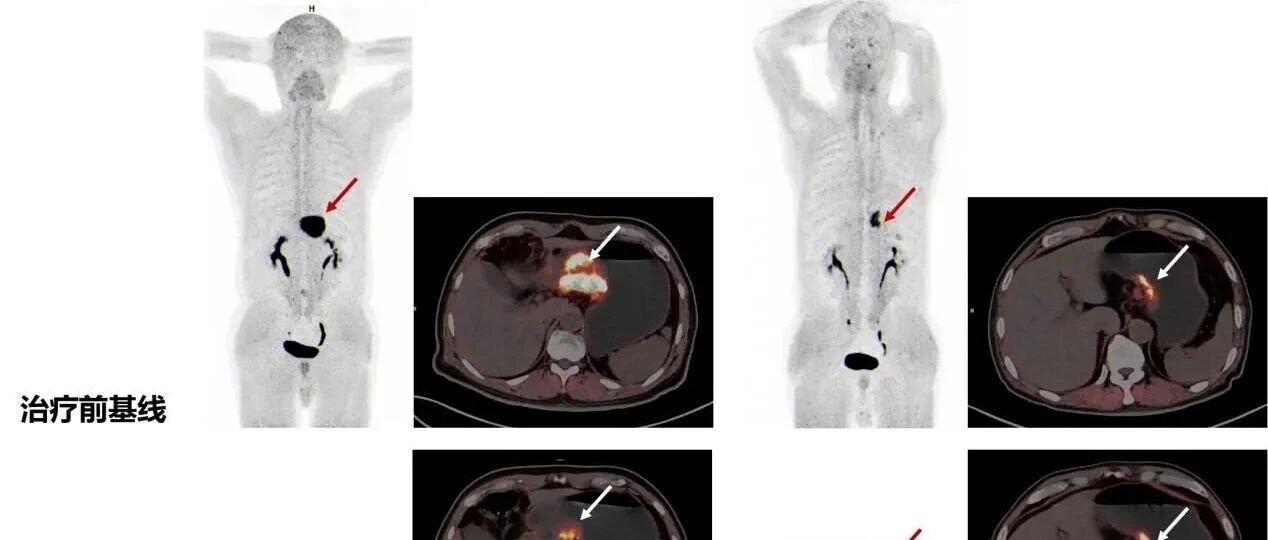

![]() ![]() 胃癌分期T3N0术前治疗效果拔群 #胃肠肿瘤符涛 #胃癌 #胃癌术前治疗 #胃癌化疗 #抖出健康知识宝藏 @抖音健康 胃肠肿瘤符涛 发布时间2026/01/04 10:00:00 | 37 | 31 | 26 | 115 | 更多 |